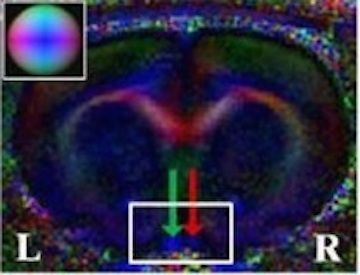

• In Vivo Evaluation of White Matter Inegrity and Anterograde Transport in Visual Systems After Excitoxic Retinal Injury with Multimodal MRI and OCT

• LC Ho, B Wang, IP Conner, Y Van der Merwe, RA Bilonick, SG Kim, EX Wu, IA Sigal, G Wollstein, JS Schuman and KC Chan

• Investigative Ophthalmology and Visual Science, 56(6), 3788-3800, June 2015.

image